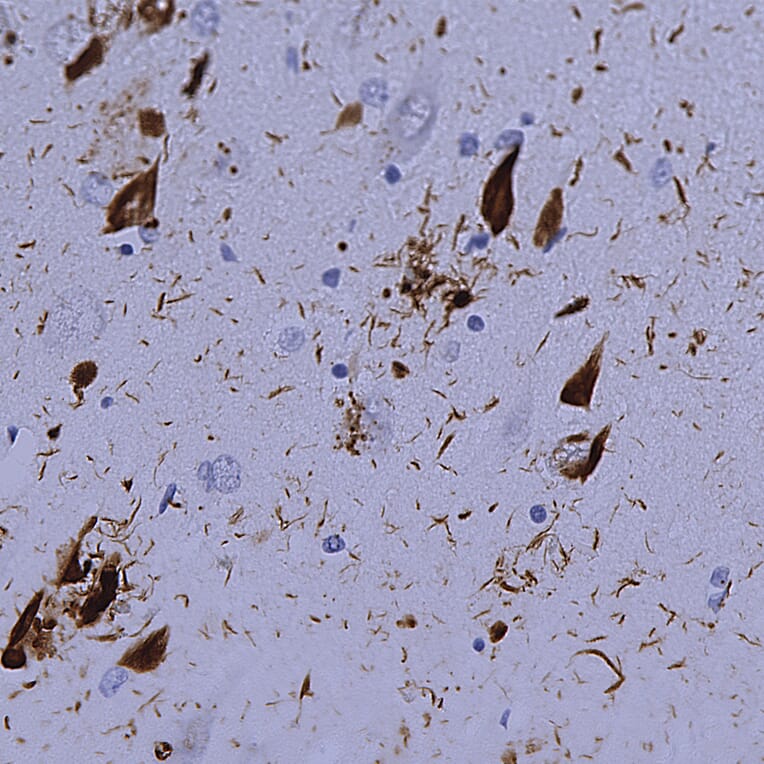

Immunohistochemistry analysis of a NBF fixed paraffin embedded human hippocampus section from an Alzheimer’s Disease case. Mouse mAb to ubiquitin, Anti-Ubiquitin Antibody [Ubi-1] (A85456) at a dilution of 1:2,000, was detected in DAB (brown) following the ImmPress method with citra buffer retrieval. Counterstained with Hematoxylin (blue). The Anti-Ubiquitin Antibody [Ubi-1] (A85456) strongly labels flame shapped tangles in pyramidal neurons and dystrophic neurites nuclei characteristic of Alzheimer’s disease. Note: this antibody performs well in testing with 4% PFA or standard NBF fixed human and rat tissues.

Immunohistochemistry analysis of a NBF fixed paraffin embedded human hippocampus section from an Alzheimer’s Disease case. Anti-Ubiquitin Antibody [Ubi-1] (A85456) at a dilution of 1:2,000 detected with DAB (brown) using the Vector Labs ImmPRESS method and reagents with citra buffer retrieval. Counterstained with Hematoxylin (blue). The Anti-Ubiquitin Antibody (A85455) antibody strongly labels the cytoplasm of diseased neurons as identified by their morphology.